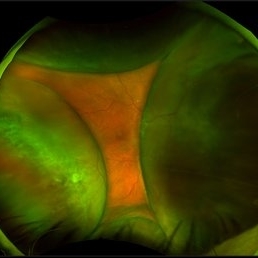

Hemorrhagic Choroidals

Hemorrhagic Choroidals

Jan 22 2025 by Danish Shabbir, Ophthalmic Technologist

78 year old female complains of suddenly vision decrease 2 days ago.

Photographer: Danish Shabbir,Retina-EyeCare Centre

Imaging device: Optos California

Condition/keywords: choroidal detachment, Retinal Detachment, retinal detachment with choroidal